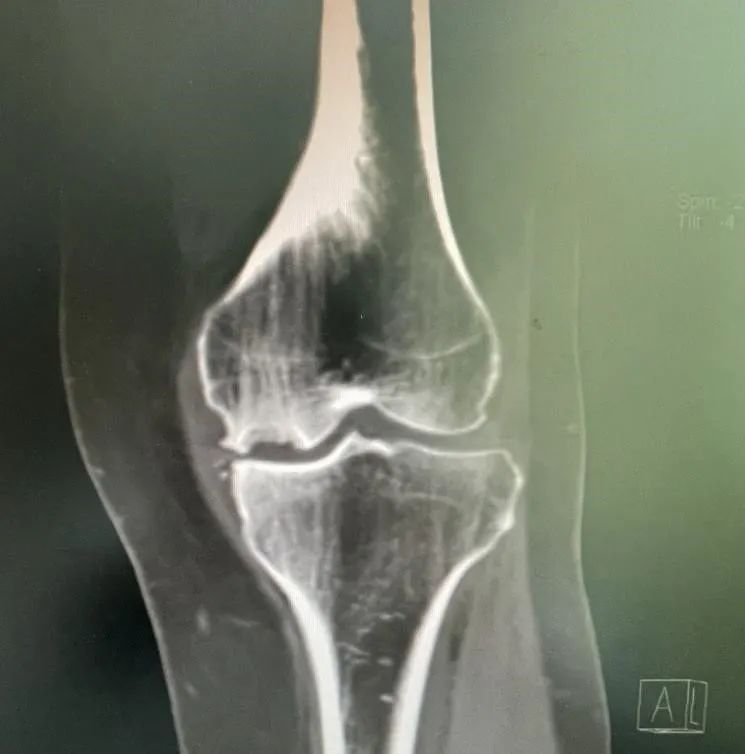

膝关节疼痛背后的真相 术前检查片 老年膝关节疼痛通常被认为是由于骨头磨损所致,但实际情况可能更为复杂。例如,73岁的梁大姐就经历了这种痛苦。她的症状包括走路困难、关节肿胀和持续的疼痛。经过详细的检查和诊断,医生发现梁大姐患有膝关节内侧自发性骨坏死,这是一种不常见的疾病。这种病症涉及到软骨的退变、软骨下骨的水肿以及骨头的坏死,这些因素共同导致了剧烈的疼痛。 单髁置换术——治疗新选择 针对梁大姐的情况,ky骨科一区的许国胜主任提出了三种手术方法:关节镜手术、全膝关节置换术和单髁置换术。考虑到创伤大小、术后恢复速度和功能恢复等因素,最终选择了单髁置换术。这种手术仅更换受坏死影响的内侧间室骨头,同时保留了外侧间室、髌股关节和交叉韧带的正常功能。与传统全膝关节置换相比,单髁置换具有创伤小、疼痛轻、恢复快等优点。 术后效果与快速康复 梁大姐在接受了内侧单髁置换术后,第二天就能下地走路,并在术后第三天出院回家。一个月后复查时,她的左膝关节内侧疼痛症状完全消失,关节活动自如。这一案例证明了单髁置换术的有效性。此外,该手术在国外已有超过30年的历史,在国内外也有超过15年的应用时间,技术成熟且效果稳定可靠。对于早期病变的患者来说,单髁置换术不仅能明显改善生活质量,还能延缓全膝置换的时间。